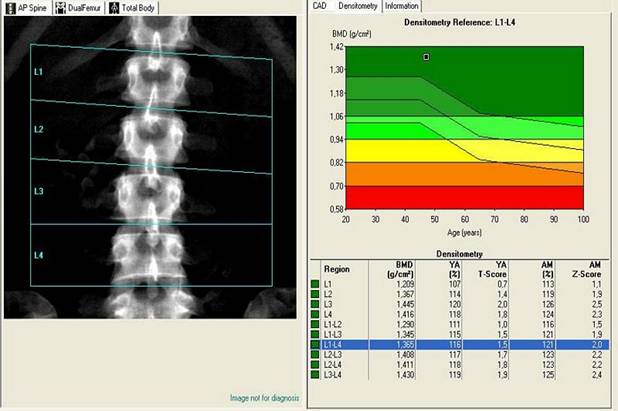

Τα αποτελέσματα της εξέτασης συγκρίνονται με αντίστοιχες τιμές από υγιή άτομα, ηλικίας 30 ετών, και εκφράζονται σε τιμές T-score. Εάν το T-score είναι ίσο με 1, τότε η οστική πυκνότητα είναι φυσιολογική. Τιμές από μηδέν έως 1 αντιστοιχούν σε οριακή μείωση, οπότε συνιστάται επανάληψη της εξέτασης μέσα σε 1-2 χρόνια. Τιμές του T-score από -1 έως -2.5 επισημαίνουν ότι το άτομο έχει κίνδυνο να αναπτύξει οστεοπόρωση, ενώ τιμές κατώτερες του -2.5 ανευρίσκονται σε ασθενείς με εγκατεστημένη οστεοπόρωση. Άτομα με αρνητικές τιμές του T-score χρειάζονται θεραπεία και ετήσιο έλεγχο της οστικής πυκνότητας. (Εικόνα Β)

(Εικόνα Β, T-score)